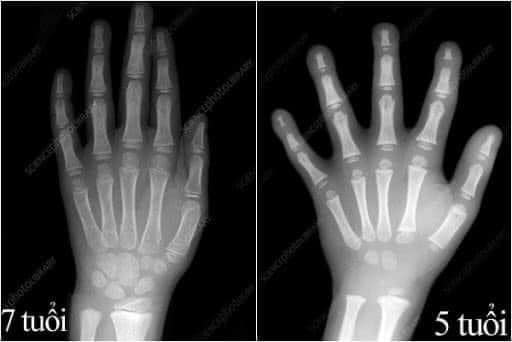

“Vì đây là ảnh chụp X-Quang xương bàn tay đứa trẻ 7 tuổi (bên trái) và bàn tay của một đứa trẻ 5 tuổi (bên phải), theo thí nghiệm của bà Ruth Swailes – Cố vấn cao cấp cải thiện trường học với hơn 25 năm kinh nghiệm trong lĩnh vực giáo dục tiểu học.

Theo bức ảnh trên, bà Ruth Swailes nhận xét về sự thay đổi rõ rệt của kích thước bàn tay, đặc biệt sụn ở bàn tay của trẻ 5 tuổi sẽ hóa thành xương khi lên 7 tuổi, và bàn tay có dấu hiệu “cứng” lại thông qua quá trình hóa học nội tiết. Quá trình này diễn ra từ 6 – 8 tuổi.

Điều này chứng minh rằng khoảng thời gian trẻ 0 -6 tuổi đặc biệt ở tuổi mẫu giáo 2,5 -6 tuổi chính là giai đoạn quan trọng để cha mẹ giúp con luyện các kỹ năng vận động tinh trước khi bàn tay con ‘cứng’ lại.